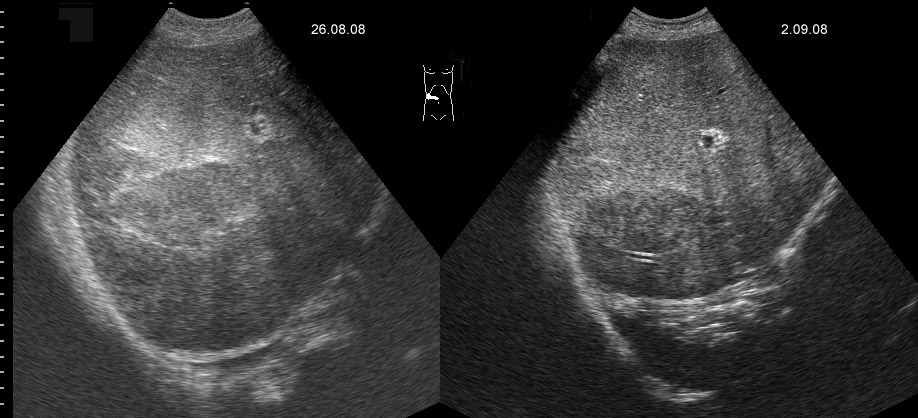

Маленький абсцесс печени до и на фоне 1 недели АБ-терапии

Плохая доступность. Был расположен очень высоко и был небольших размеров.

Решено было вести консервативно.